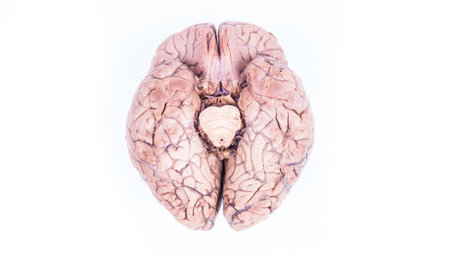

real human brain isolated on white

Human brain model on a neutral background, top view. Scientific study and education concept.

Human brain on a red background. Top view. Copy space.

human brain on white background